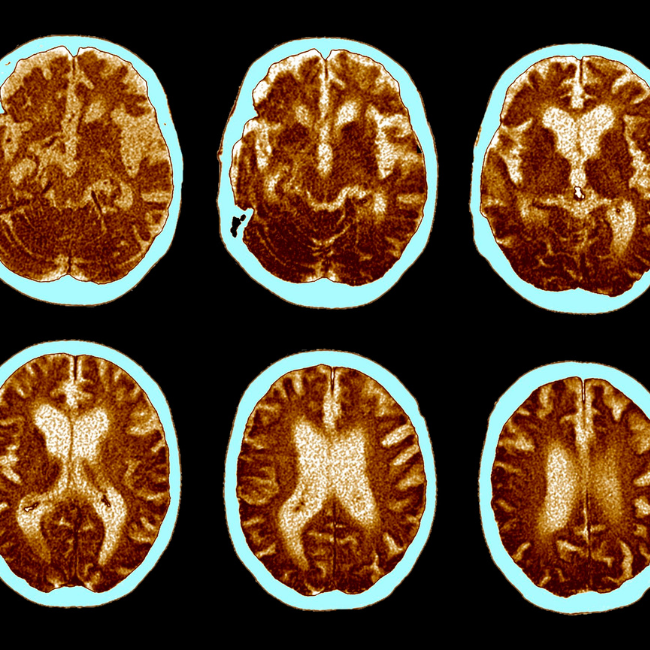

- 신경영상학적 검사: 뇌의 구조와 기능을 평가하기 위해 신경영상학적 검사가 사용될 수 있습니다. 이는 MRI(Magnetic Resonance Imaging)나 CT(Computed Tomography) 스캔을 포함할 수 있습니다. 이러한 영상 검사는 뇌의 손상 또는 변화를 확인하는 데 도움이 됩니다.